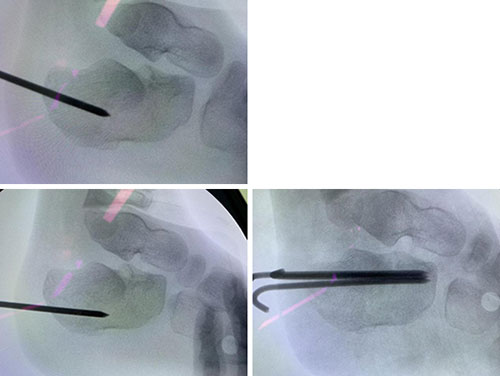

上午安排了一台手术,患儿因高处坠落导致跟骨骨折,由外地来济后辗转数家医院却无法及时手术。来到小儿骨科就诊后,王延宙主任立即收治入院,上午即安排完成手术。手术采取了微创复位固定治疗,效果良好。

翘拨复位后用克氏针固定,复位情况良好